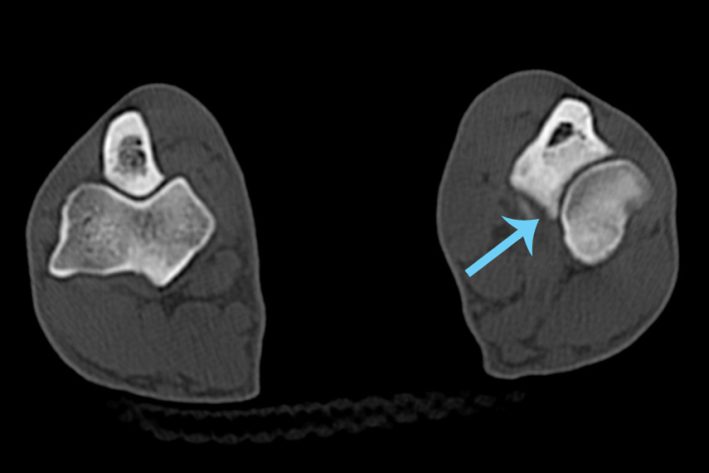

SLT 3D Rekonstruktion Ellbogen Ellbogenarthrosen FCP

Ellbogengelenk mit fortgeschrittenen Gelenksarthrosen. Der Pfeil markiert das abgebrochene Knochenfragment am inneren Processus Coronoideus.

Fragmentierung des Processus Coronoideus